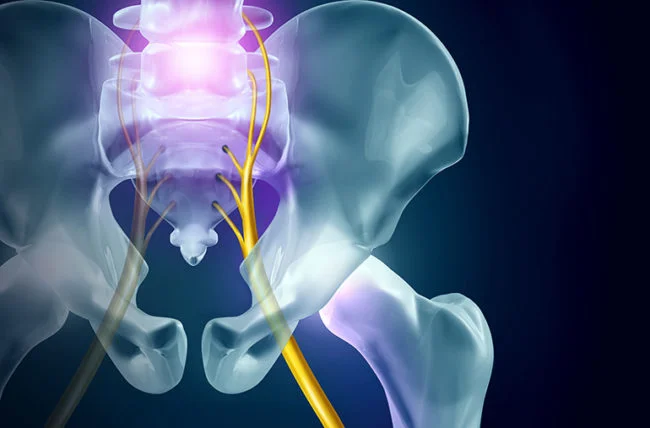

What is Sciatica?

Sciatica is not a condition itself but a symptom caused by irritation of the sciatic nerve, the largest and widest nerve in the human body. The sciatic nerve is located in the lower back, runs through the buttocks, and down the back of the leg into the calf. Sciatic pain often affects only one side of the body and can range from mild discomfort to intense, debilitating pain. Common causes include herniated discs, spinal stenosis, and bone spurs.

The medical term for sciatica is lumbar radiculopathy and refers to disease involving the lumbar spinal nerve root, typically caused by a compression of the spinal nerve root.